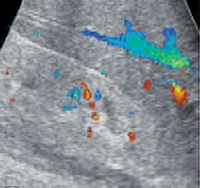

3. Визуализация почек.

Для того чтобы рассмотреть почки и мочевыводящие пути, чаще всего используется ультразвук. В некоторых случаях назначают компьютерную и магнитно-резонансную томографию, ангиографию (исследование сосудов) и др.

При проведении пробы Зимницкого выявляется изогипостенурия. УЗИ почек свидетельствует о снижении толщины паренхимы и уменьшении размера почек. Снижение внутриорганного и магистрального почечного кровотока выявляется на УЗДГ сосудов почек. Рентгенконтрастную урографию следует применять с осторожностью из-за нефротоксичности многих контрастных препаратов. Перечень других диагностических процедур определяется характером патологии, ставшей причиной развития ХПН.